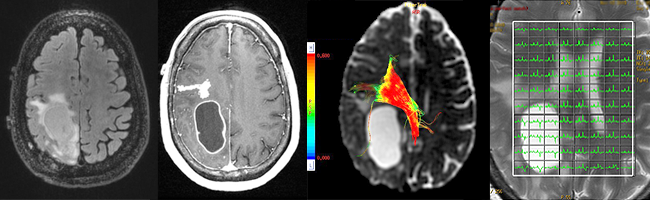

Neuroradiology focuses on imaging and therapies to diagnose and to treat disorders of the adult and pediatric brain, spine, neck, and central and peripheral nervous system. The UCSF neuroradiology group is comprised of internationally recognized experts in every one of these disciplines, and in the latest state-of-the-art imaging with CT, MRI, MEG and molecular modalities such as PET. The group has expertise in the full array of neurologic disease, including brain tumors, stroke and other vascular disorders, spine disease, neurodegenerative diseases, and brain malformations. With 12 full-time neuroradiologists across our campuses, we are one of the largest divisions of neuroradiology in the United States.

Patients are referred to UCSF neuroradiology from all over the world. Each year we perform and interpret over 14,000 CTs, 22,000 MRIs, 250 myelograms, more than 1,000 diagnostic angiograms, over 650 interventional procedures, and more than 500 spinal procedures including biopsies, nerve root block, epidural injections of steroids and specialized procedures including vertebroplasty and kyphoplasty. For example, we offer special expertise and apply advanced cutting edge MRI techniques for the diagnosis and monitoring of patients with brain, skull base and ENT tumors, traumatic brain injuries, the range of pediatric brain and spine disorders as well as for patients with spine related pain. Because we perform an unusually high number of procedures each year, referred from a variety of specialists, we have gained enormous clinical and scientific expertise. That expertise leads to more precise diagnoses and better clinical judgment and skill. It also directly facilitates our ability to help patients and their doctors by sharing our skills in “seeing,” detecting, and treating abnormalities. This allows us to provide informative consultations to referring physicians and to suggest proper interventions.

Neuroradiology Advanced Techniques and Technologies

At UCSF we have the highest quality imaging equipment and use the appropriate one for the task at hand in order to achieve crisper, better, more detailed, higher resolution images for patients.